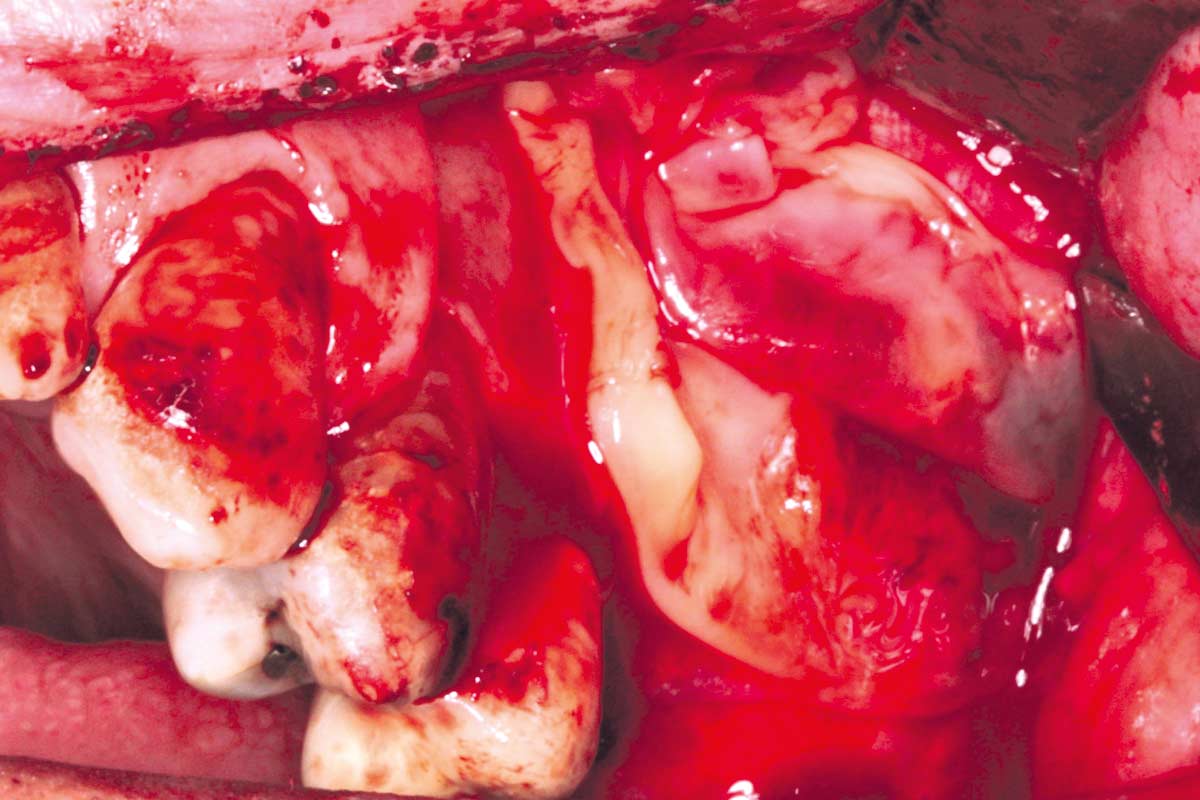

07/35 - Removal of the cyst from the sinusMaxillary sinus cyst removal using the Crocodile Technique and subsequent lateral sinus lift - Dres. C. Scognamiglio and A. Perucchi